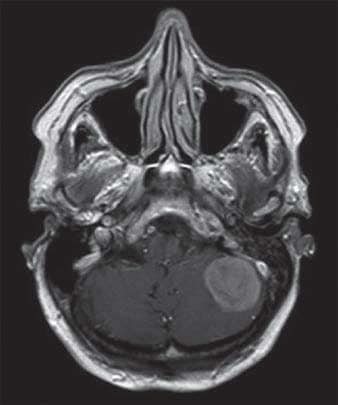

IRM d’une femme de 88 ans atteinte d’un méningiome de la fosse cérébrale postérieure